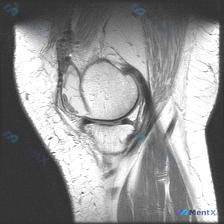

看到这个病例挺有代表性,整理了完整的分析思路分享给大家。 病例与影像基础信息 这是一份单张膝关节矢状位MRI影像,临床关注点是"半月板异常",需要基于现有影像做分析。 影像的核心征象整理如下: 1. 序列与定位:膝关节中部偏内侧矢状位,考虑为PDWI或T1加权像,适合显示半月板、韧带解剖结构 2....

刚整理了一份很有临床参考意义的病例读片资料,分享一下思路,大家一起讨论。 病例基本信息 临床关注点:患者自述/临床怀疑存在半月板异常,提供单张膝关节MRI T1序列矢状位图像供分析。 影像读片结果 先把读片的核心结果整理出来: 1. 图像与解剖:图像对比度良好,为膝关节矢状位T1序列,可清晰显示股骨...

看到一个很典型的临床-影像矛盾病例,整理出来和大家分享思路。 病例核心信息 这是一张膝关节矢状位MRI单张图像,临床关注点为「半月板异常」,我们先来看影像的全面评估结果: 1. 骨骼结构:股骨远端、胫骨近端、髌骨轮廓完整,无明显骨皮质中断或骨折 2. 关节软骨:股骨、胫骨关节面软骨信号均匀,无明显剥...